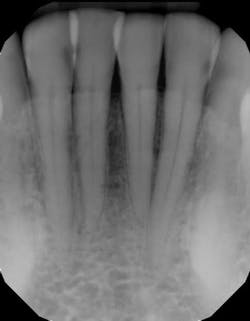

In another example, a young patient had been using e-cigarettes for five years. He started vaping as a method to quit smoking traditional tobacco products thinking vaping was a healthy alternative. Because of its ease of use, he smoked a cartridge of one of the more popular vaping products a day. Admittedly, he also drank energy drinks (high sugar content), stating that his mouth was often dry after vaping. This combination led to rampant decay with smooth-surface lesions and future tooth loss (figure 3).

Many advocates of vaping claim that e-cigarette use and vaping poses 5% the health risks of traditional tobacco smoking and claim its use to be helpful in getting people to quit.11 This particular use does have merit and has helped many individuals quit smoking. Unfortunately, these studies have only analyzed e-cigarette use in former smokers using vaping as a way to stop smoking. The studies have not looked at the health effects of nonsmokers who start vaping because of the perceived innocuous health effects and because it “tastes yummy.” In addition, these studies have not looked at vaping in middle school and high school individuals, the group where e-cigarette use is increasing the most in percentage of use. Because of this, a tidal wave of oral health problems is heading our way.